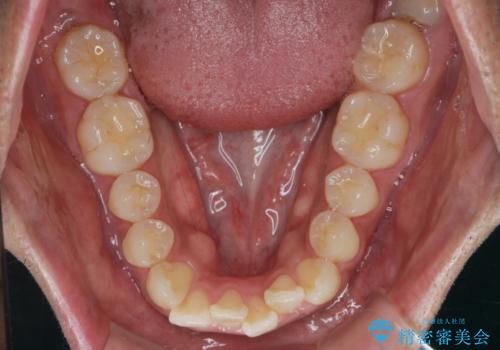

- 前歯のガタつきをきれいにしたい、と矯正治療を希望され来院されました。

マウスピース矯正インビザラインを用いてガタつきをきれいに並べていきます。

外側に傾斜していた前歯の角度も良くなり、「前歯の見た目が良くなった。」、と喜んでいただくことができました。